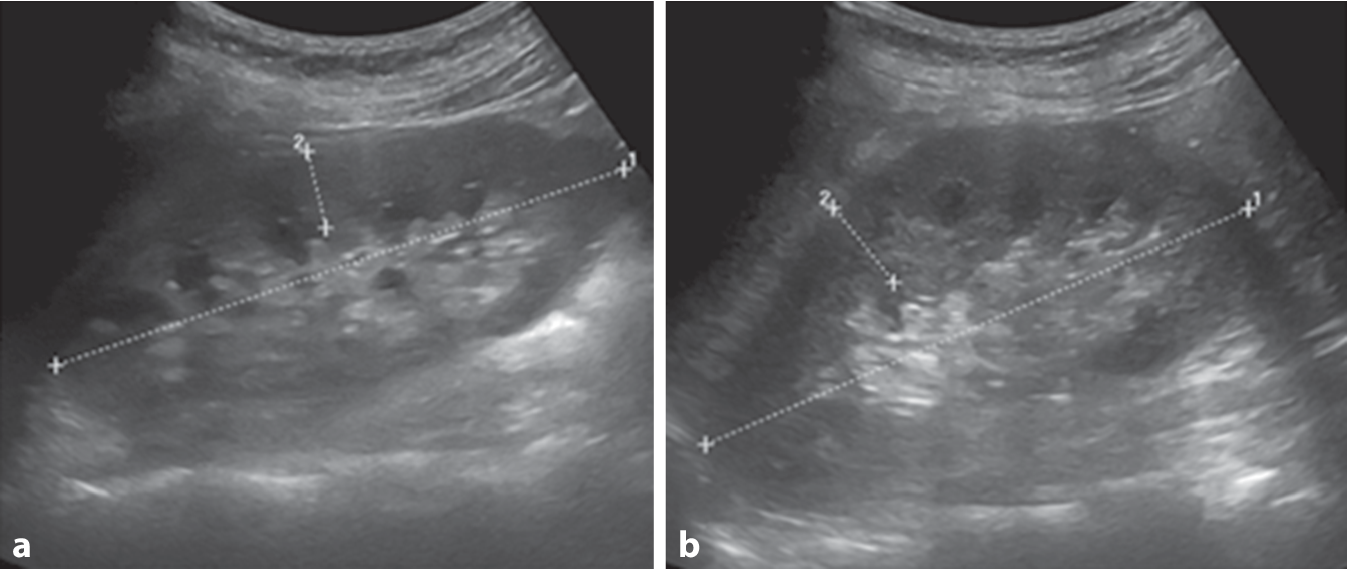

Nativradiologisch bestanden keine typischen arthritischen Veränderungen der Hände und Füße noch Zeichen einer Kristallarthropathie der Knie und Hände (Abb. 1). Bei normwertiger Nierenfunktion und unauffälligem Urinsediment konnten in der Abdomensonographie kleine Konkremente im Nierenbeckenkelchsystem (Nierengrieß) beidseits ohne Harnstauung dargestellt werden (Abb. 2). Zudem ergab sich elektroneurographisch kein Hinweis auf ein Karpaltunnelsyndrom bei ebenfalls unauffälligem Befund der Magnetresonanztomographie der Lendenwirbelsäule.

Abb. 2

Sonographisch orthotope Lage und regelhafte Größe der Nieren beidseits, a rechts 11,6 cm lang, b links 11 cm, mit beidseits regelhafter Parenchymdicke, a rechts 1,59 cm, b links 1,91 cm, und kleine Konkremente im Nierenbeckenkelchsystem (Nierengrieß) beidseits ohne Harnstauung